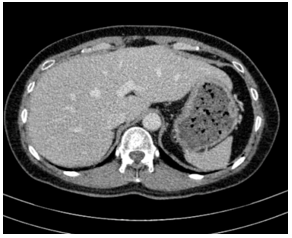

- Cắt lớp vi tính ổ bụng:

Hình ảnh cắt lớp vi tính ổ bụng có tiêm: chưa phát hiện tổn thương nghi ngờ thứ phát

- Cắt lớp vi tính ổ bụng: Không phát hiện tổn thương bất thường.